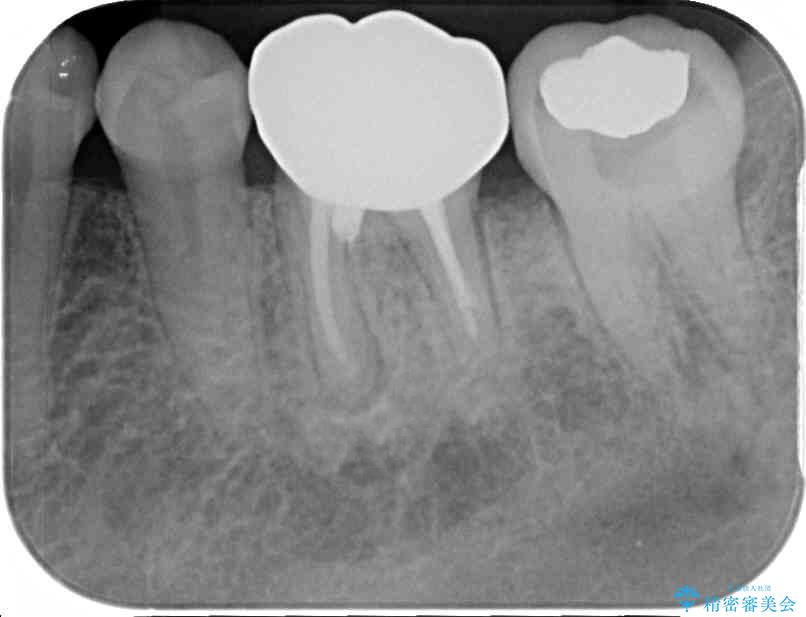

以前むし歯治療をした後から定期的に痛むことがあるとのことで、レントゲン写真より神経組織が失活していることが予想されました。

銀歯を外すと神経組織の一部が取り除かれており、歯根に付け根に穴が空けられている状態でした。

出血の原因は以前の治療で空けられた穴であると考え、封鎖をするとともに根管治療を行い、その後オールセラミッククラウンにて補綴治療を行うこととしました。

術後6ヶ月でレントゲン写真を撮影したところ、出血の原因であった穴付近の溶けていた骨が回復している様子が認められました。

• むし歯で歯茎から血が出てくる オールセラミッククラウンでの補綴治療 治療前画像